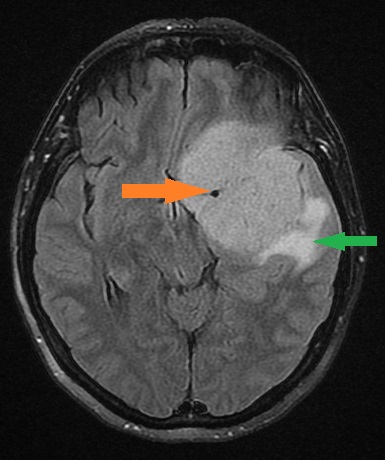

Cechy, które mogą budzić większą czujność

Zgodnie z wytycznymi European Association of Neuro-Oncology (EANO), pewne cechy w MRI mogą sugerować bardziej agresywne zachowanie guza:

- rozległy obrzęk mózgu,

- niejednorodne („plamiste”) wzmocnienie po kontraście.

Nie oznacza to automatycznie nowotworu złośliwego, ale zwykle wymaga dokładniejszej oceny i ostrożniejszego planowania leczenia.